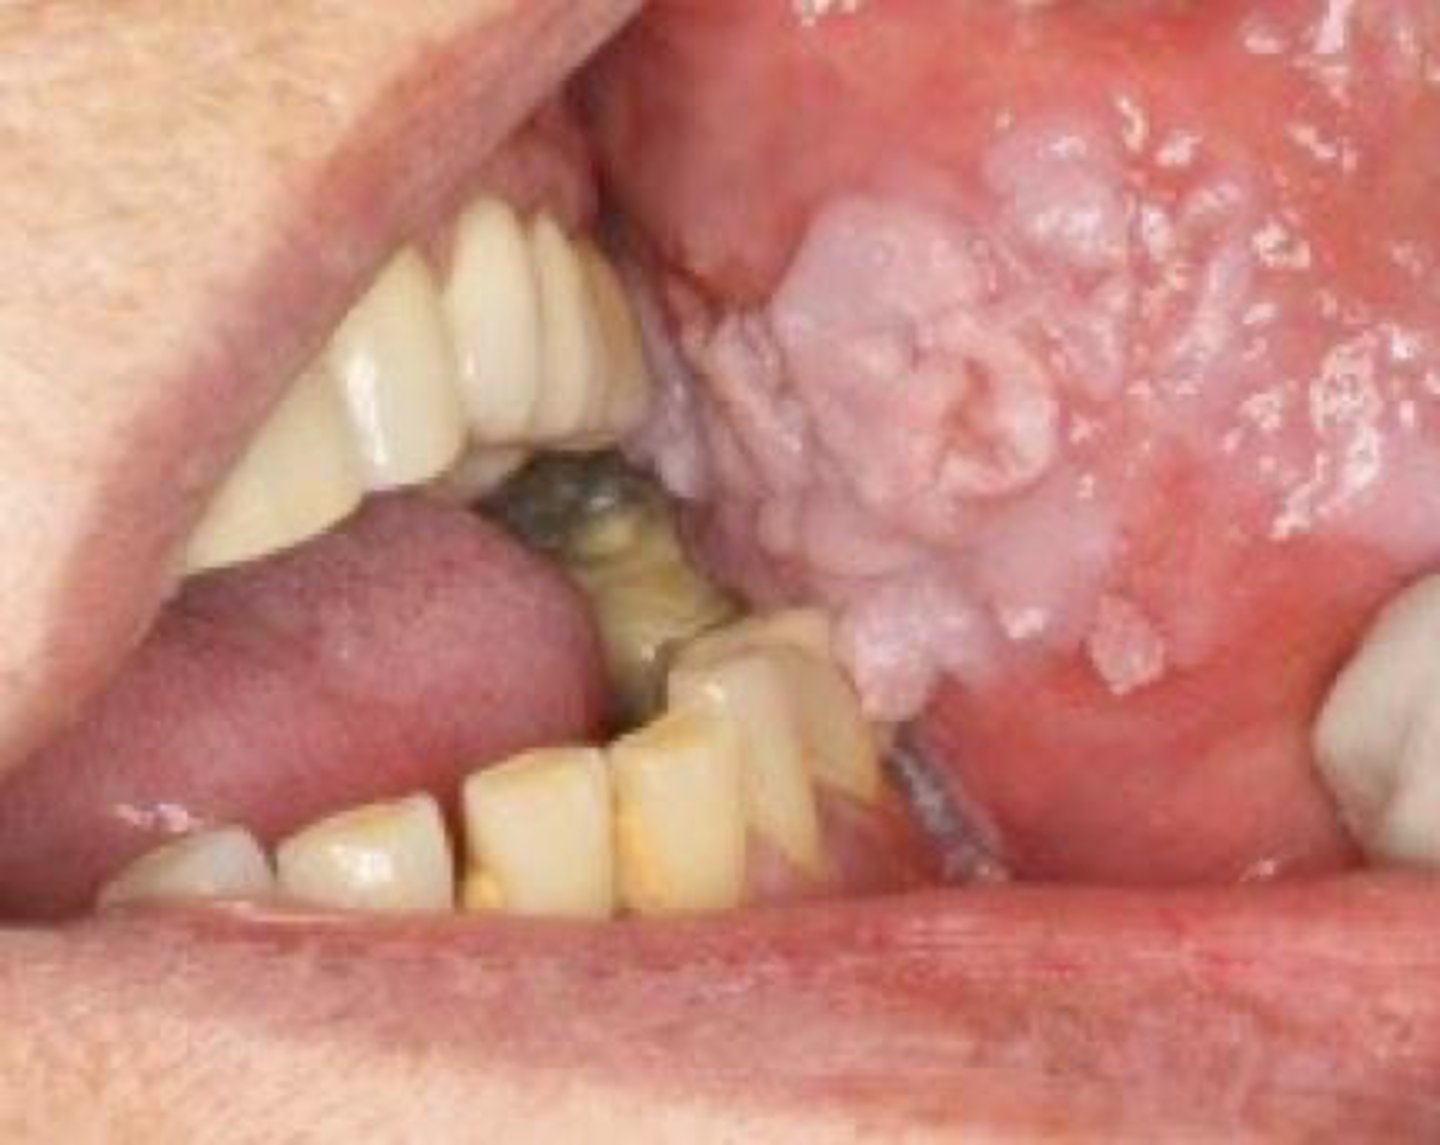

A slow-growing, thick, white, warty lesion on the buccal mucosa of an older adult who uses smokeless tobacco is most likely:

verrucous carcinoma

What is the BEST treatment for verrucous carcinoma?

surgical excision